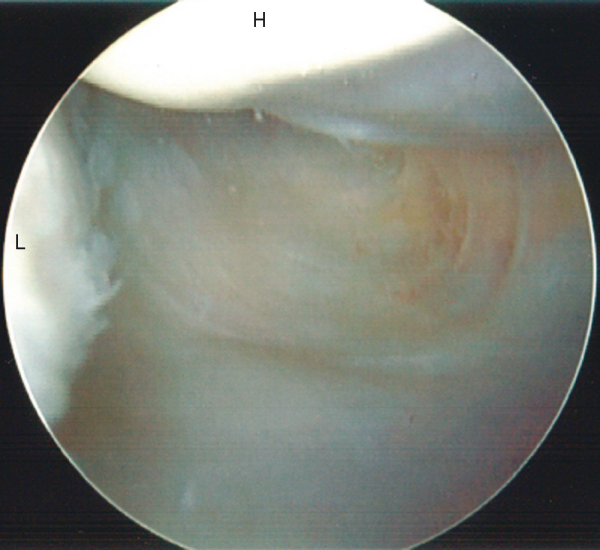

The rotator cuff insertion can be followed posteriorly with the aid of humeral rotation. The bare area of the humeral head, which often contains remnants of old vascular channels, can be visualized and borders the attachment site of the infraspinatus tendon (

Fig. 1-23

). Continuing to sweep inferiorly around the posterior rotator cuff insertion will bring the arthroscope into the posterior axillary pouch (

Fig. 1-24